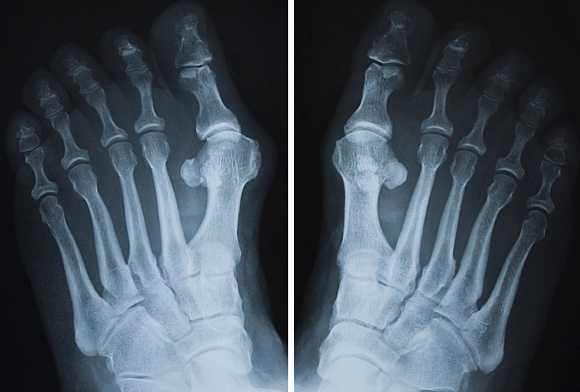

Ревматические поражения

Рентген кистей рук при ревматоидном артрите - важная диагностическая процедура, которая позволяет точно выявить стадию развития заболевания. Главными рентген-признаками данной патологии являются припухлости мягких тканей сустава. Также об артрите свидетельствует незначительное сужение межсуставной щели и визуализируемый остеопороз. На более поздних стадиях развития патологии будут видны эрозии костей, которые имеют вид некрупных краевых дефектов в суставных концах костей. В эпифизах костей фаланг пальцев могут виднеться округлые просветления.

При проведении рентгена кистей рук с функцией увеличения изображения можно выявить нарушение целостности замыкающих пластинок уже на первых стадиях развития ревматоидного артрита. По мере прогрессирования заболевания будет наблюдаться ухудшение картины - сустав будет становиться всё уже, появятся очаги эрозии, станет ярче выраженность остеопороза. В результате разрушения суставных концов кости могут появиться подвывихи.